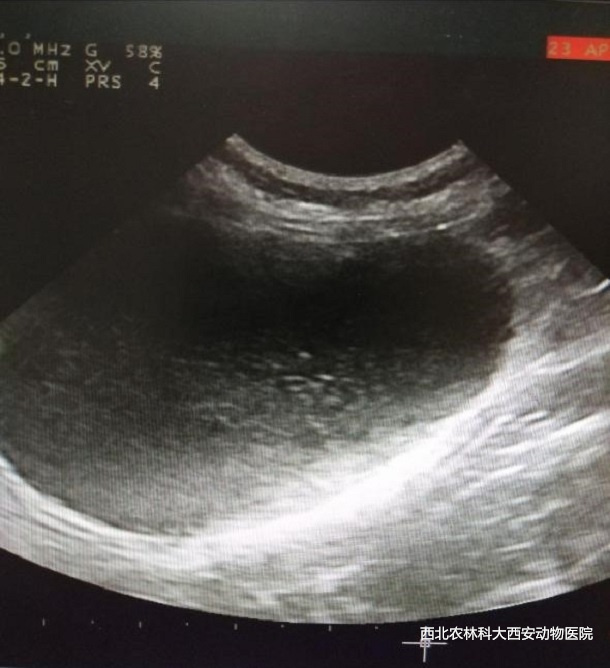

輔助檢查:血常規(guī)、生化、血?dú)夂湍虺猎鼨z查異常指標(biāo)見(表1),超聲檢查:可見膀胱內(nèi)散在高回聲影像,膀胱粘膜欠光滑見(圖1)。

圖一